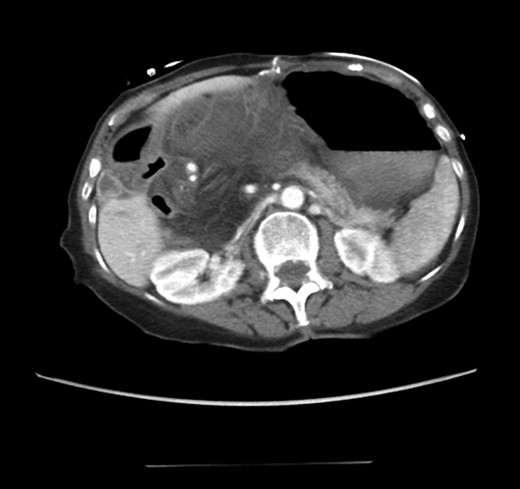

An 81-year-old female with a medical history of CAD with stents, hyperlipidemia, hypothyroidism, GERD, recent UTI, pancreatic cyst, constipation, anemia and leukopenia presented to the ED with a 1 day history of mild, diffuse and cramping abdominal pain. The patient was unable to give an accurate history, but the son at bedside supplemented this reporting that for several years the patient had been experiencing ill-defined abdominal discomfort. Physical exam showed a soft abdomen with mild tenderness and no evidence of peritonitis. A CT scan of the abdomen and pelvis with IV and PO contrast (Fig. 1) showed edematous changes to the mesentery of the small and large bowel with swirling of vessels indicative of internal hernia. The stomach was also noted to be distended with both air and fluid as a consequence of posterior compression by the hernia contents (Fig. 2). A surgical consult was obtained, a nasogastric tube and Foley catheter were placed, antibiotics were started, and the patient was taken for an exploratory laparotomy. Upon entering the abdomen through a vertical midline incision, 1.5 l of ascites was drained revealing a diffusely edematous mesentery. A large portion of the small bowel was seen to be herniated through the Foramen of Winslow (Fig. 3). A Kocher maneuver and division of the gastrocolic ligament were then performed to allow release of the herniated small bowel. It was at this time that, in addition to small bowel, a large portion of the ascending and transverse colon was noted to be herniated through the foramen of Winslow. The small bowel was also seen to be torsed about its own mesentery. Normal anatomy was restored and the bowel noted to be healthy and viable with peristalsis (Fig. 4). Due to the large size of the foramen after reduction and enlargement, it was deemed best to leave it open to prevent any further incarceration or strangulation. The abdomen was closed and the patient tolerated the procedure well. At a follow-up visit 2 months later, the patient had well-healed incisions, was doing well, tolerating a diet, and gaining weight appropriately.

Loops of bowel between IVC, liver, and lesser curvature of the stomach. Arrow small bowel. Arrow head stomach.

Diagnosing an internal hernia is frequently accomplished using physical exam and CT imaging. Abdominal X-ray does have some nonspecific findings suggestive of internal hernia but is usually inadequate for diagnosis. Diagnosis of a foramen of Winslow hernia, however, is only accomplished in 10% of patients preoperatively [3]. As previously mentioned this diagnosis is rare and often presents with vague obstructive type symptoms. This likely contributes to the low occurrence of accurate preoperative diagnosis. However, several radiographic findings were seen in this patient that suggested a foramen of Winslow hernia preoperatively. First, there is visible swirling of the mesentery on the CT scan that is indicative of internal hernia (Fig. 1). Second, there are loops of small bowel that can be visualized between the IVC and the edge of the liver in a supra renal position along the lesser curvature of the stomach (Figs 1 and 2). When compared to a CT of the abdomen and pelvis obtained 4 years prior to presentation, there is actually evidence that this patient had a non-obstructing foramen of Winslow hernia at that time as demonstrated by bowel being visualized in the lesser sack (Fig. 5). These findings, especially small bowel along the lesser curvature of the stomach, are inconsistent with normal anatomy and strongly indicative a foramen of Winslow hernia.